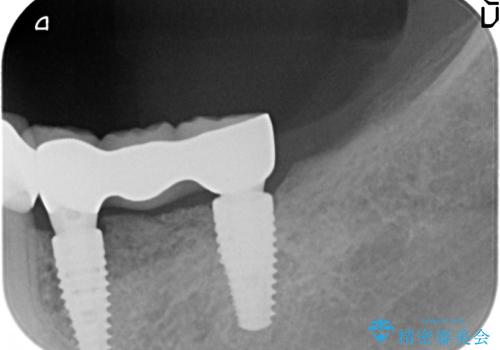

- 91万円(ストローマンインプラント×2・骨造成・チタンカスタムアバットメント×2・フルジルコニアクラウン×3)費用は治療当時の料金となります

インプラントを埋入することで入れ歯のように取り外しをする必要がなくしっかりと噛めるような状態になり、大変治療結果に満足していただくことができました。